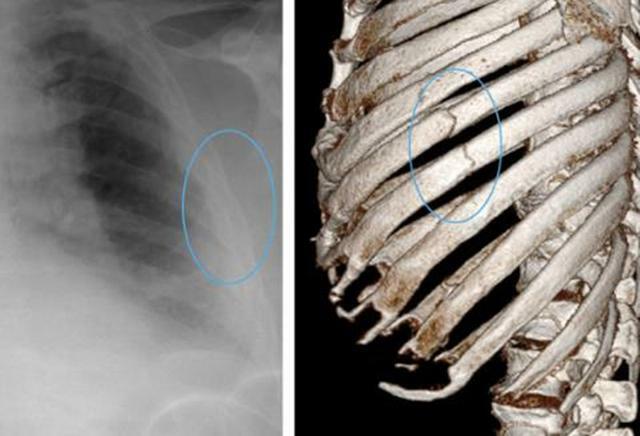

醫生建議:一部分患者的疼痛會消失,如果不適持續存在,可考慮進行胸部X光檢查,如果胸部X光檢查正常,但依然有持續疼痛或壓痛,可考慮進行CT檢查和超聲評估。

醫生建議:這時候需要明確骨折跡象,可考慮胸部X光檢查,但胸痛往往與呼吸問題相關,建議進行胸部CT掃描。由於有一些肋骨骨折無移位,X光片難以確認,需要進一步CT橫斷面掃描。

由此可見,CT掃描檢查是診斷肋骨骨折的最佳手段。有些骨折X光不一定能看得清。肋骨骨折可由輕微的碰撞引起,也可由嚴重的車禍造成,最容易發生骨折的在第4-7肋骨,不僅因為它們長而且細,並且缺乏上方1-3肋骨的鎖骨和肩胛骨的保護。往下則是第10-12肋骨,它們的一端是懸空的,不固定在任何骨頭上,彈性大,也不容易骨折。